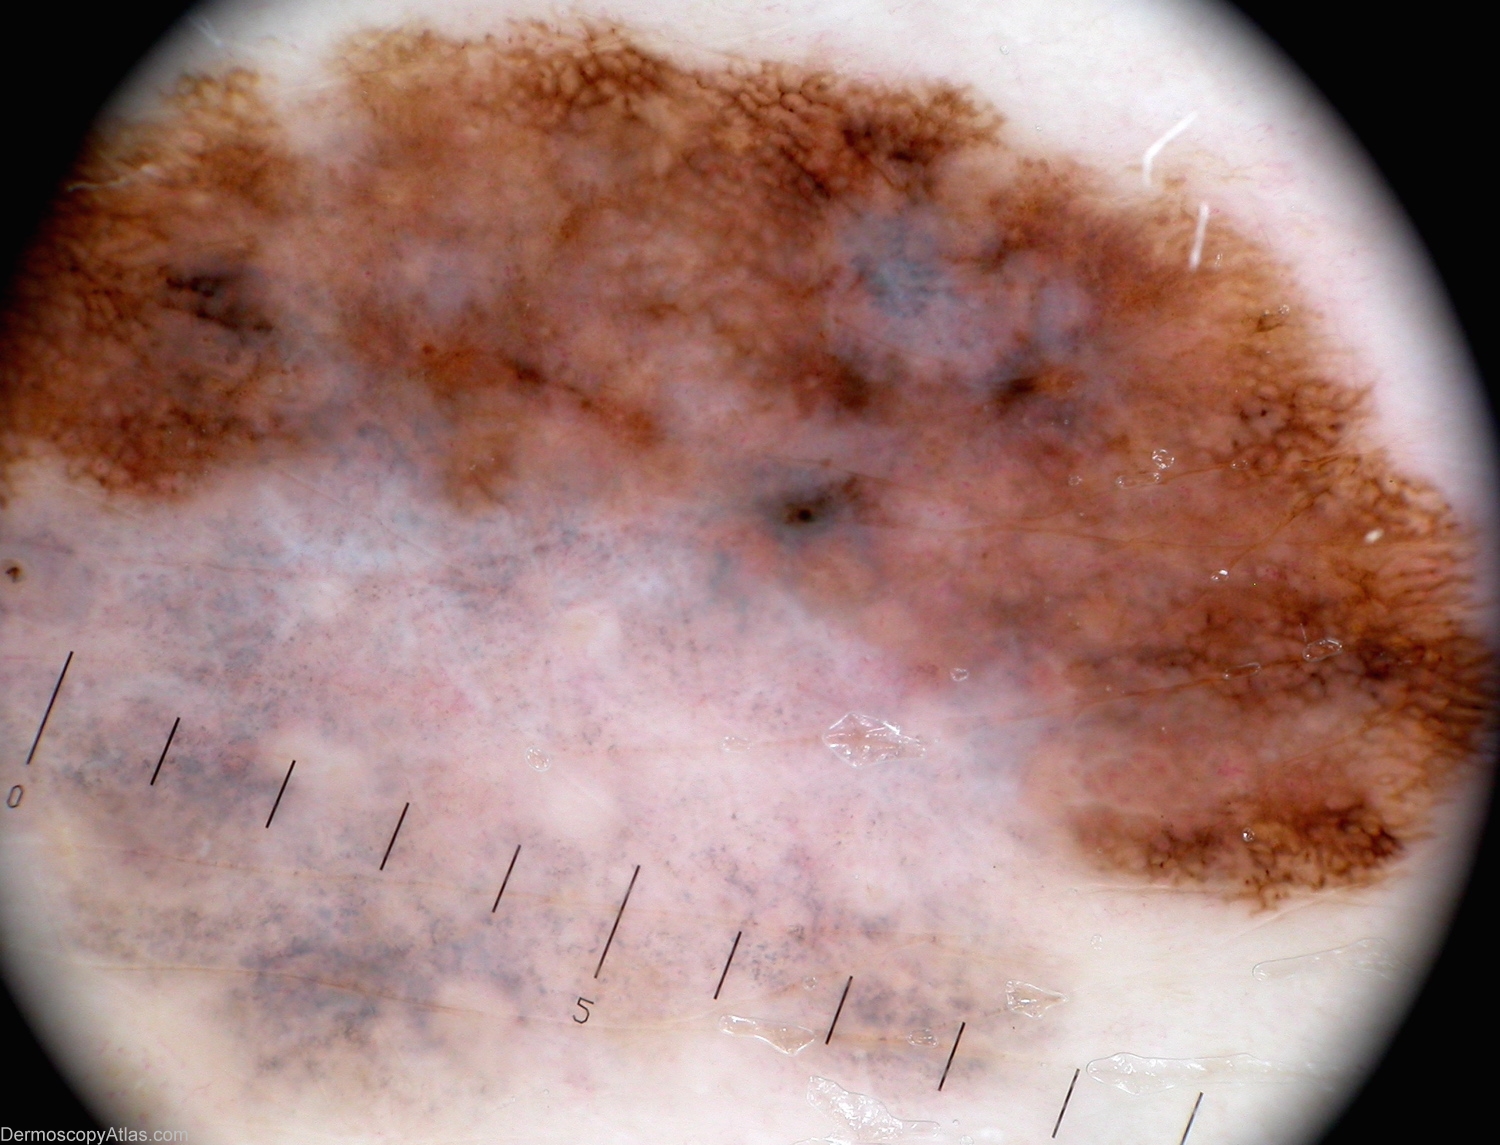

Diagnosis: Melanoma invasive

View